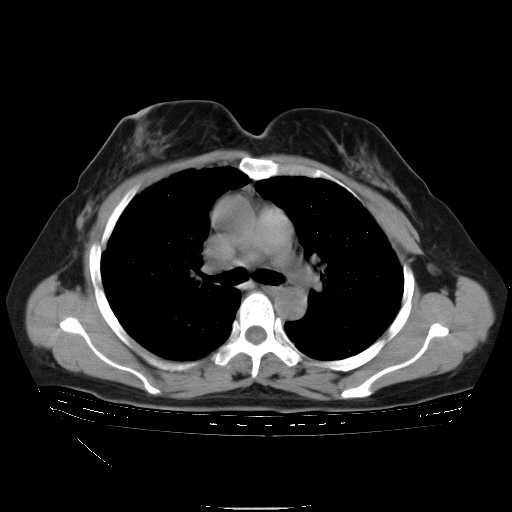

下面是今天刚刚做的,在上海治疗,吃了家属也说不清的一种药,一个月1万左右,

考虑  腺癌肺内转移,治疗较前病灶缩小、减少

肺癌并肺内转移,这种疾病治疗后在影像上看略有好转,不是很显著,但是肿瘤治疗效果影像只是一方面。

支持肺癌并肺内淋巴管炎,  原发灶小了,但转移较前片明显了.

支持右肺下叶周围型肺癌并肺内淋巴管炎,  原发灶小了,但转移较前片明显了.。

标准的细支气管肺泡癌呀!治疗后病情有所控制,也没治愈的迹象!

支持右肺下叶周围型肺癌并肺内淋巴管炎;病灶有所控制。